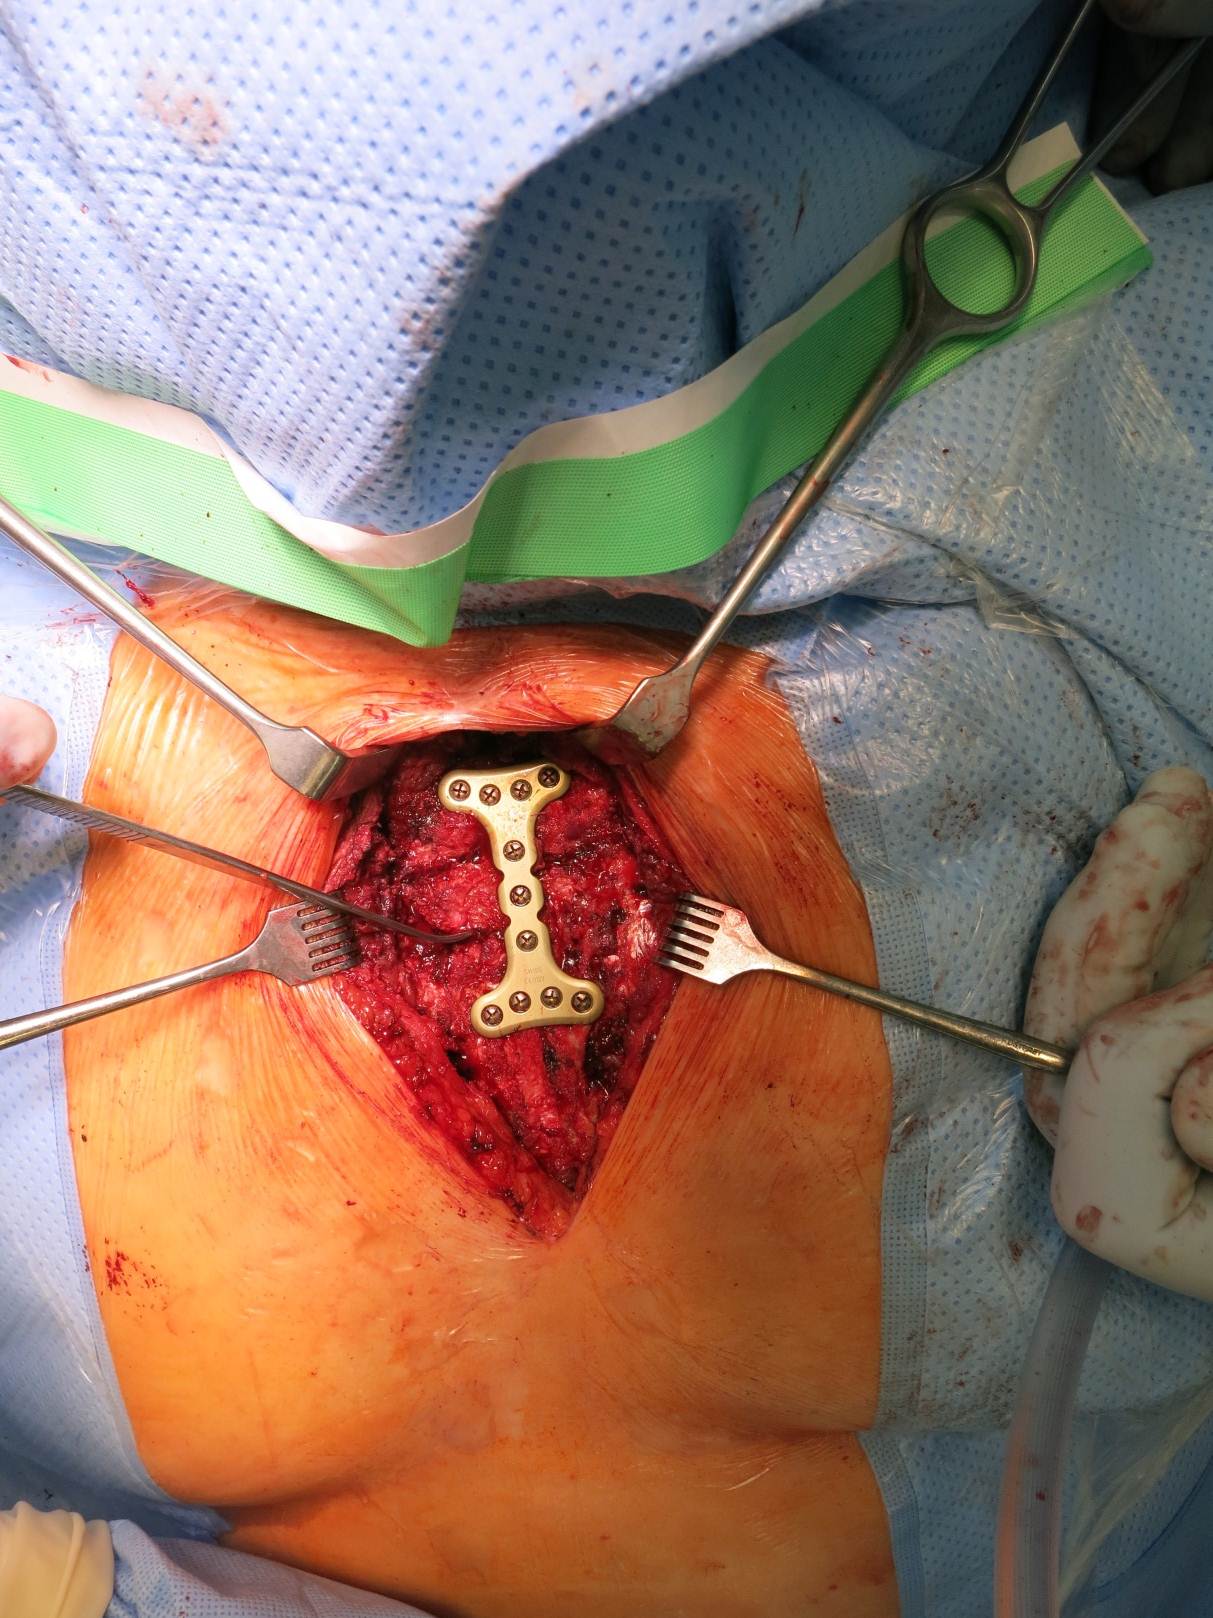

Case image provided by W Long, Portland, OR

Fall from 4-meter height

Mechanism of injury: An 81 year old woman fell onto her back from a height of 4 meters. (Fig 6a-d) She sustained a multiple sternal fracture concomitant with a fracture of the 5th thoracic vertebra resulting in an unstable injury of the trunk. Fortunately she did not show any neurologic deficit or paraplegia.

Diagnosis: Complex sternal fracture with multidirectional instability (longitudinal fracture of the manubrium, transverse fracture involving 3 levels of manubrium and corpus sterni) Concomitant to this was a fracture of the 5th thoracic vertebra (AOB2.1).

Treatment: The sternal fracture has been managed by open-reduction and internal fixation with a locked plate osteosynthesis (MatrixRIB, I-Plate) through an anterior approach in the mid-line. b The thoracic spine has been managed employing dorsal instrumentation (internal fixator th4-th6).

Post-operative outcome: The wounds and bone healed uneventfully. Breathing was possible spontaneously without any restrictions. The patient reported on a significant reduction of the pain immediately after the operative procedure. Mobilization on the ward started on the first day after the procedure. No complications such as secondary failure, non-unions, pain or deformity of the chest wall could be seen during the follow up examinations of 6 and 12 weeks and 6 and 12 months.